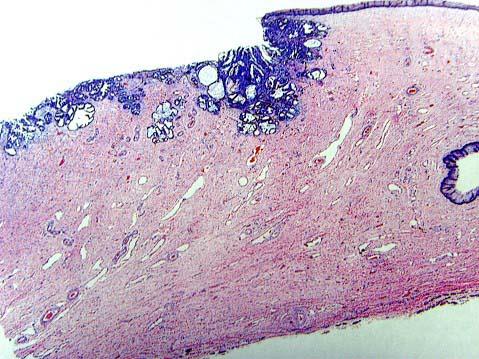

问题 女性,30岁,检查宫颈糜烂,活检CINⅢ级可疑原位癌,行LEEP刀治疗,镜检如图,应诊断为 ( )

选项 A.宫颈原位癌局灶微浸润 B.宫颈原位癌 C.宫颈上皮CINⅢ级 D.宫颈上皮CINⅢ级伴原位癌 E.宫颈浸润性鳞状细胞癌

答案 A